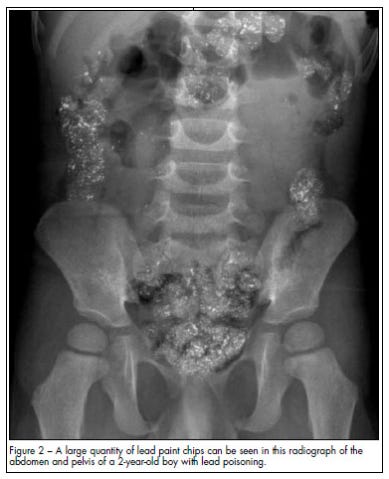

UNICEF estimates that 1 in 3 children - up to 800 million globally…

Have blood lead levels at or above 5 µg/dl.

“Lead exposure is especially dangerous to children’s developing brains and can result in reduced intelligence quotient (IQ), attention span, impaired learning ability, and increased risk of behavioural problems.”

Source: https://www.consultant360.com/articles/lead-toxicity-young-boy